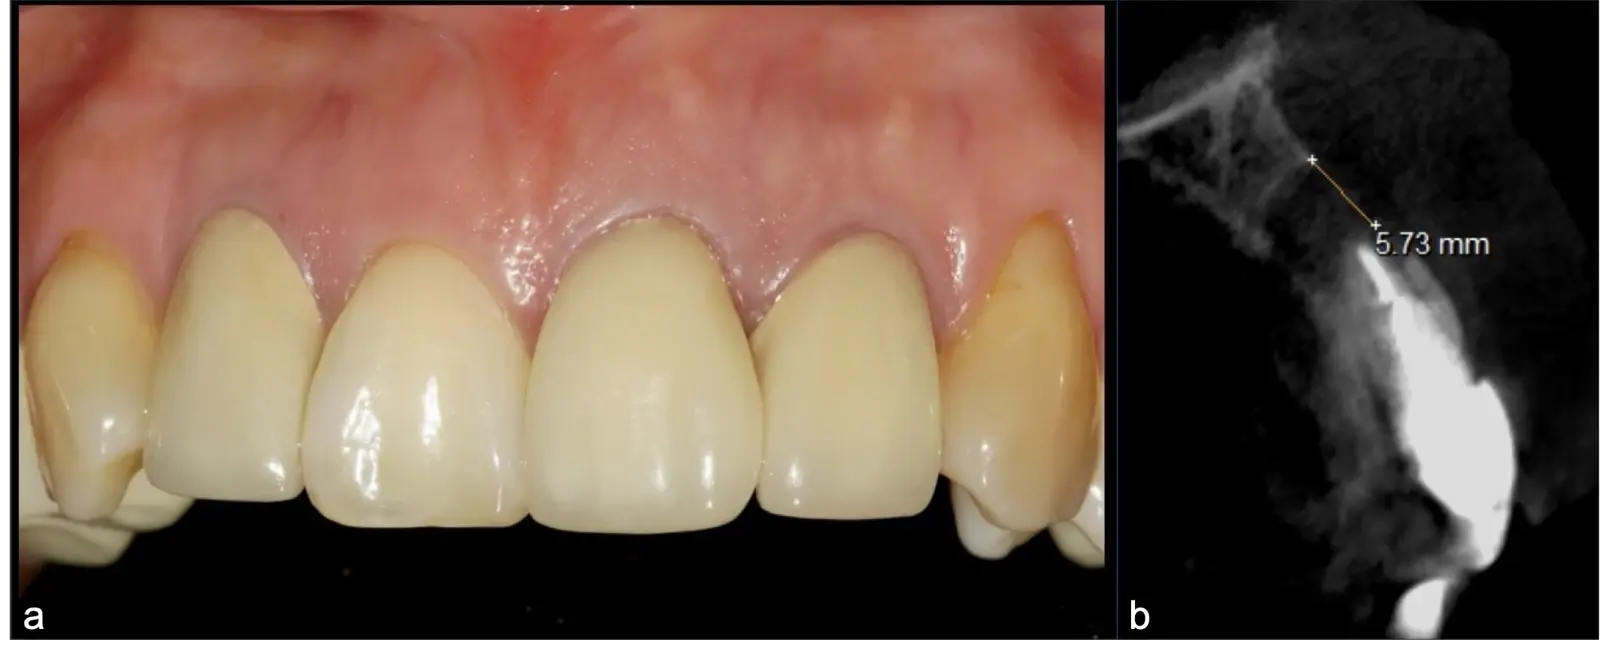

Los tratamientos endodónticos tienen una predictibilidad de éxito variable (20-90%).1 Sin embargo y con cierta frecuencia (15%), pueden aparecer complicaciones a nivel apical2 posterior al tratamiento, o incluso cuando la pieza ya posee la restauración protésica definitiva.3 Estos escenarios no deseados pueden presentarse con sintomatología persistente o esporádica y estar acompañados de imágenes radiolúcidas/hipodensas apicales.

El origen puede ser bacteriano (colonias bacterianas persistentes4, patología periodontal asociada5, reinfecciones por falta de sellado coronal), mecánico (preparación deficiente, fractura de instrumentos, fracturas radiculares6, extravasación de material de obturación7 con ó sin compromiso de estructuras vecinas) y anatómico (conductos accesorios poco permeables o calcificados)8 (Figuras 1 - 4).

La microcirugía endodóntica apical busca conservar la mayor cantidad de longitud de raíz y de hueso circundante sano para no afectar la estabilidad de la pieza.11 Por ello, es ideal el uso de microscopios, elementos de magnificación, instrumental específico (insertos de ultrasonido endodónticos) y materiales de sellado eficientes para el tratamiento retrogrado. Su éxito es alto y evidencia una cicatrización ósea completa en el 74% de los casos al año de tratamiento.12 Cabe destacar que este logro está asociado también, a predictores propios de cada paciente, como la edad, tipo de pieza, profundidad de sondaje y extensión de la lesión.1 El uso complementario de la tomografía computarizada es resaltante como el instrumento imagenológico de elección para la etapa de planificación microquirúrgica,13 ya sea para una ejecución a mano alzada o con guías prefabricadas.14,15